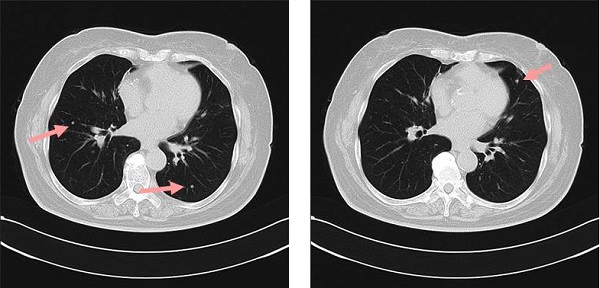

M因子からみた肺癌の手術2006年 脳転移を有する非小細胞肺癌の外科

非小細胞肺がんの脳転移における全脳照射の意義は がん情報サイト